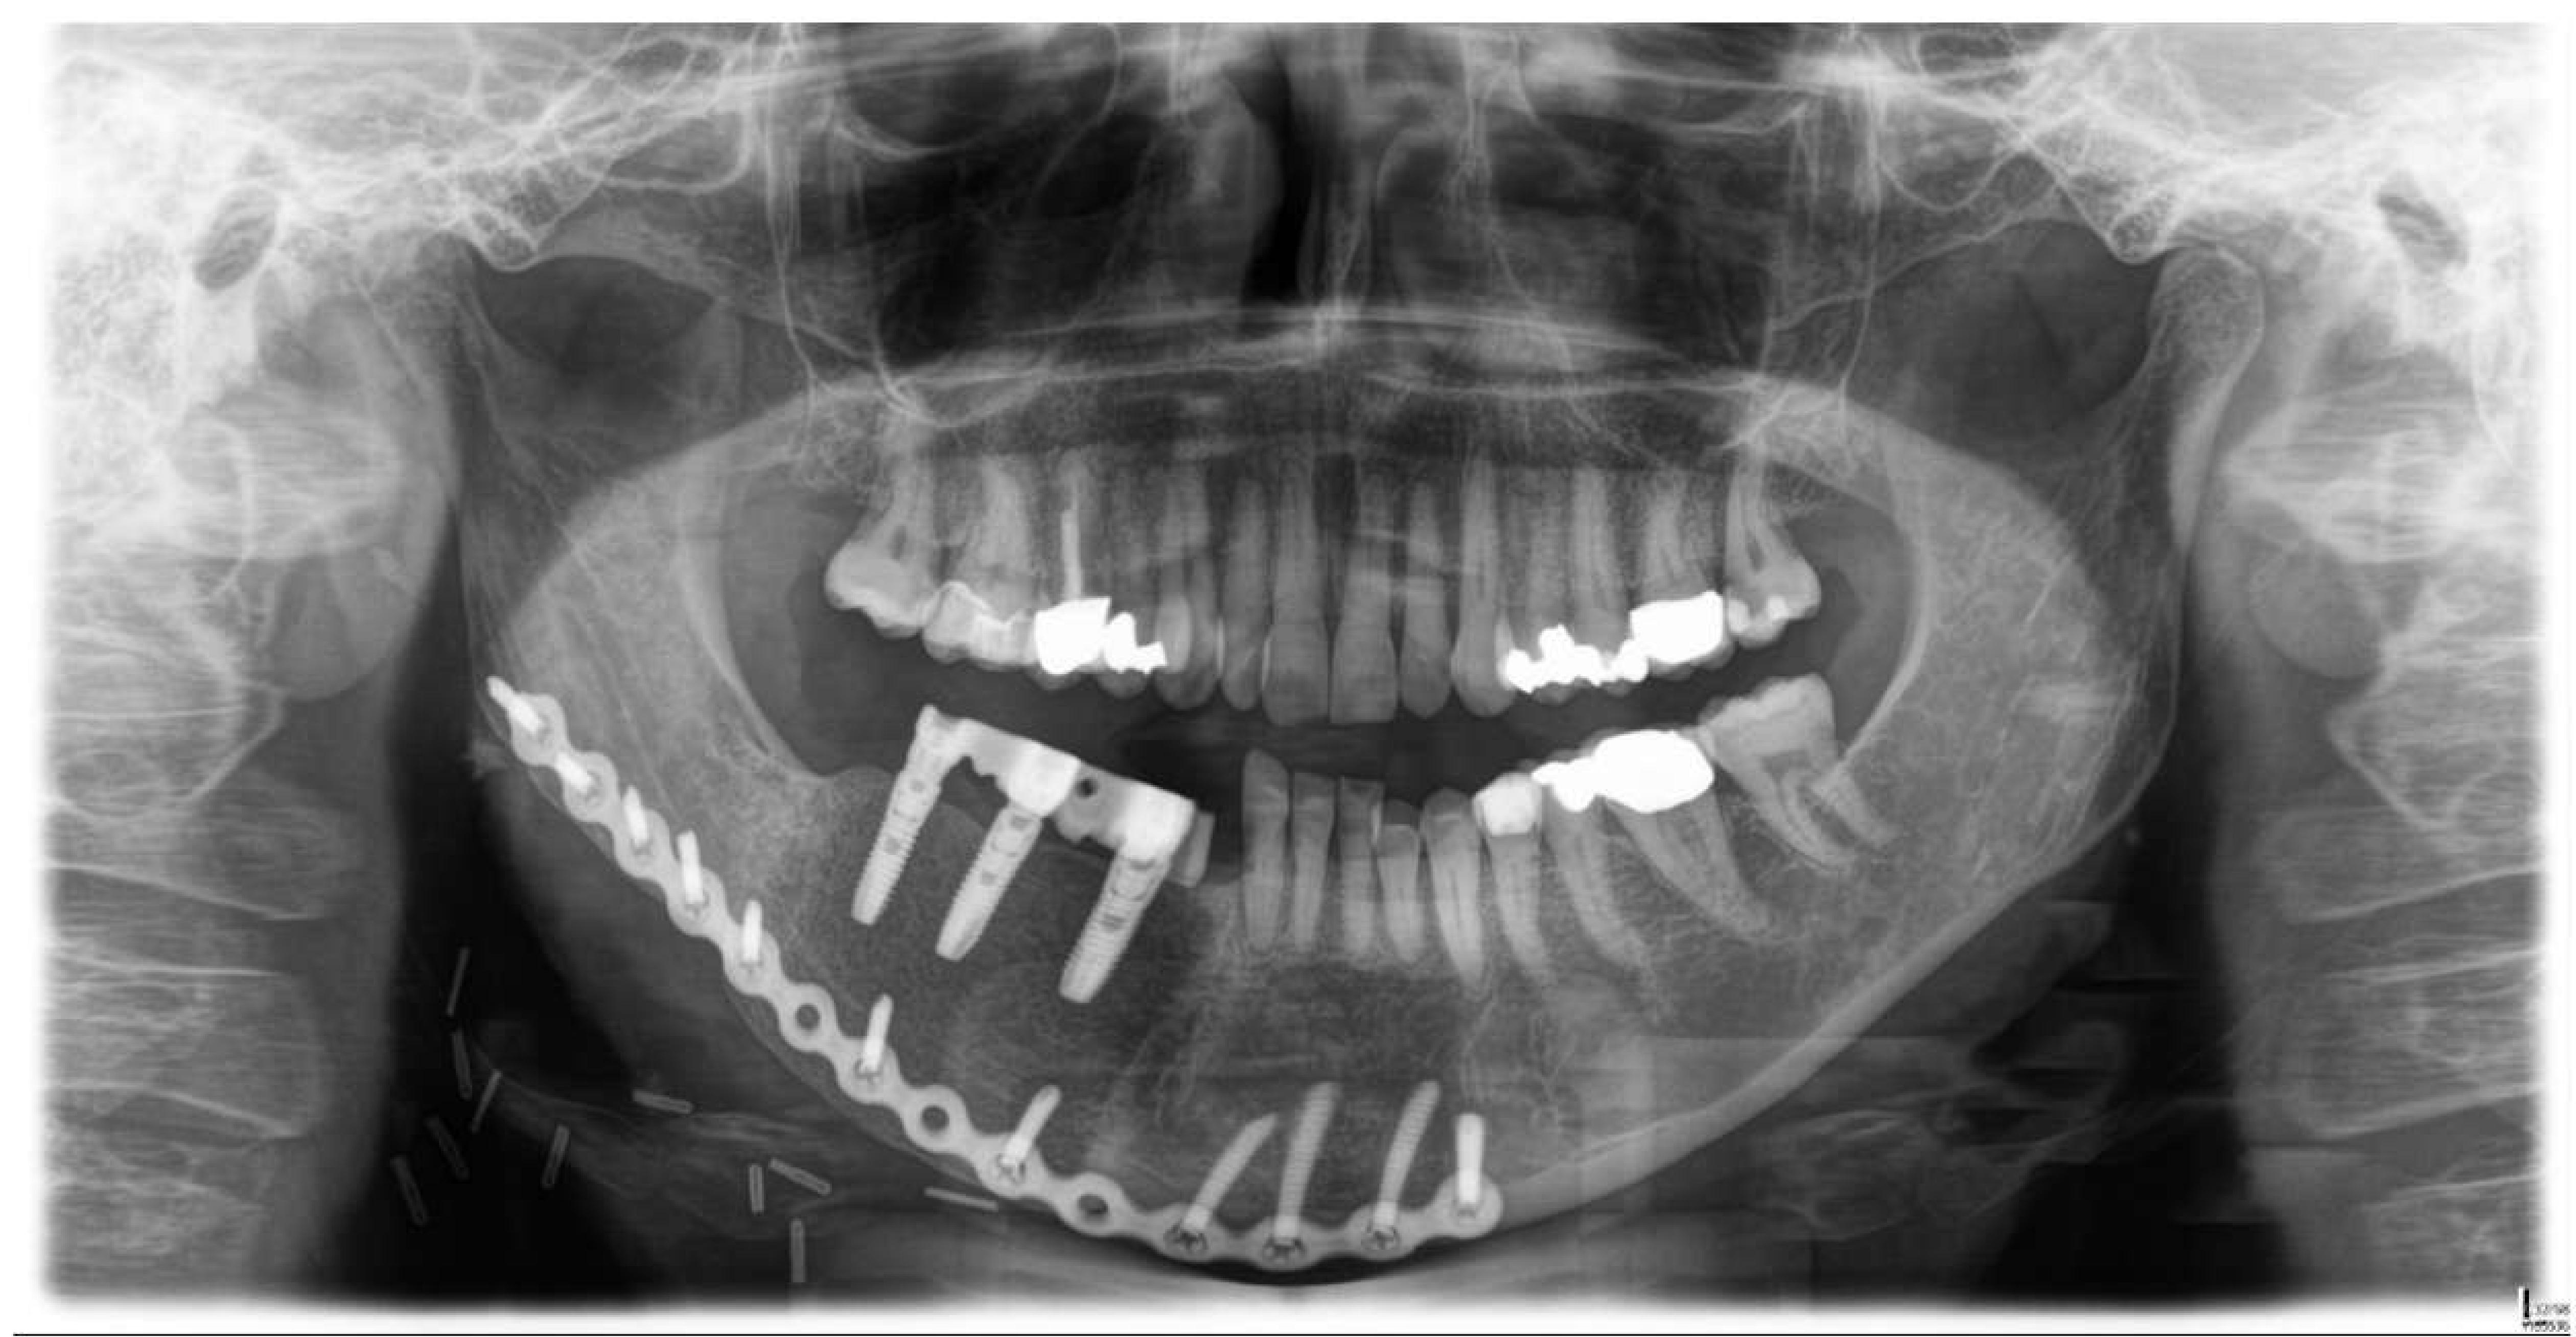

2. Case Presentation